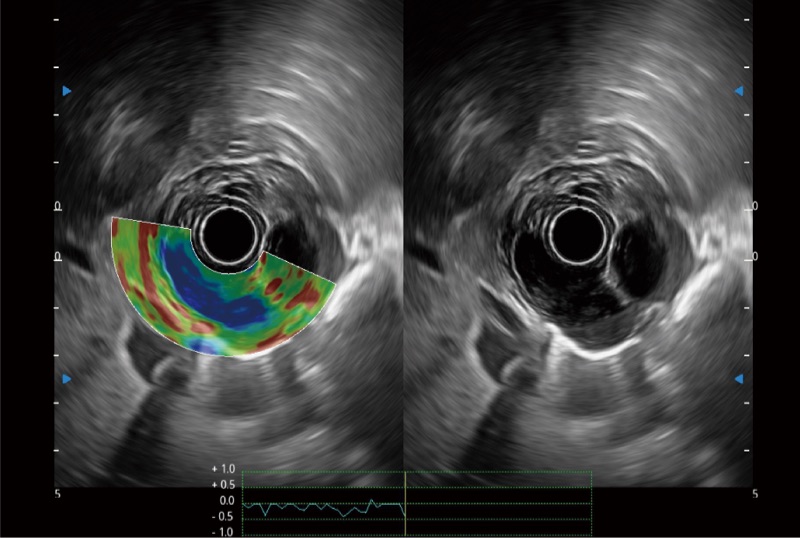

位移矫正技术

不可靠区域自动剔除

弹性定量分析软件

肝左叶和肝静脉的横截面